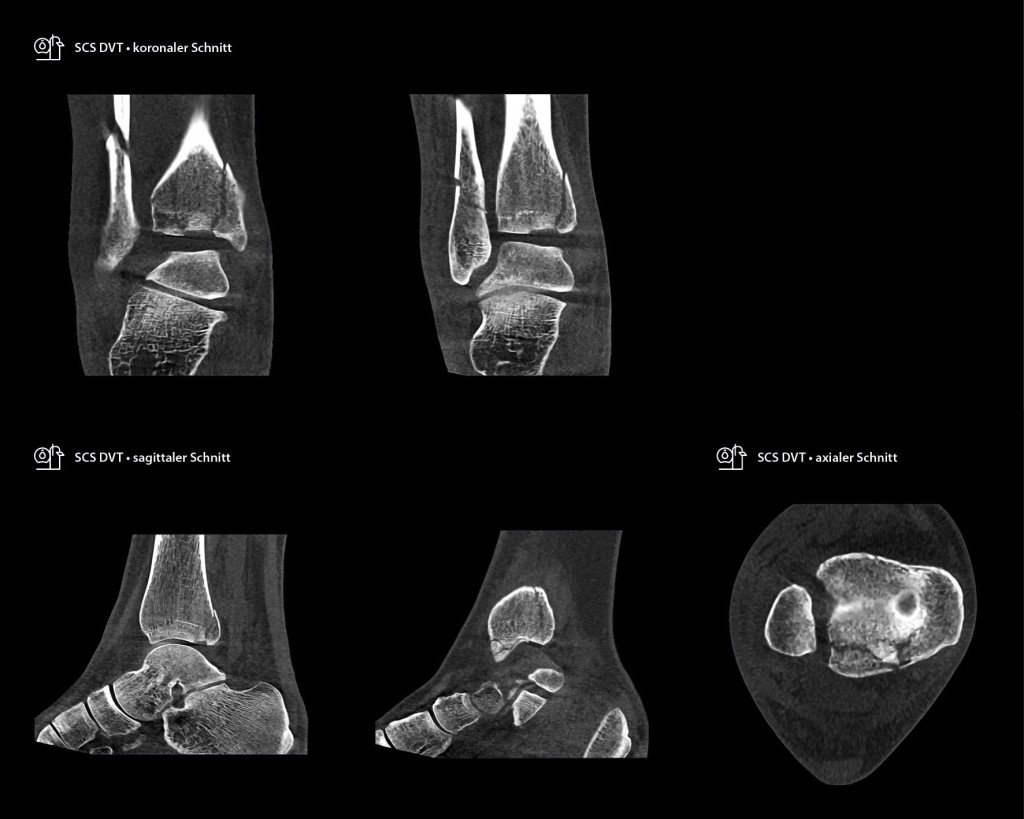

Die Untersuchung mit dem SCS DVT zeigte einen gravierenderen Befund, der auch Einfluss auf die Indikation des operativen Verfahrens hat. Es bestätigte sich die Mehrfragmentfraktur der distalen Fibula, sowie die Innenknöchelfraktur. Entscheidend ist aber die Möglichkeit der exakten Beurteilung der dorsalen Frakturen der Tibia. Diese sind aufgrund der Summation im konventionellen Röntgen nicht zu erkennen gewesen. Neben der Fraktur des Volkmann-Dreiecks mit entsprechender Instabilität der dorsalen Syndesmose zeigt sich eine Impression eines Gelenkfragmentes und eine Fraktur der dorsomedialen Tibia (Abb. 2–4). Die gesamte effektive Strahlendosis betrug 1,5 μSv für das 2-D-Röntgen + 1,4 μSv für das DVT im SULD-Protokoll, insgesamt 2,9 μSv. Bei einer konventionellen CT-Untersuchung wären es 1,5 μSv + 21,4 μSv = 22,9 μSv gewesen. Bei einer sofortigen Untersuchung mit dem DVT hätte die Dosis 1,4 μSv betragen. Aufgrund dieser komplexen Verletzungsmuster bestand die Indikation zur Operation in Bauchlage zur Versorgung der dorsalen Frakturen der Tibia und Fibula über einen dorsolateralen Zugang sowie perkutan zur Verschraubung des medialen Malleolus.